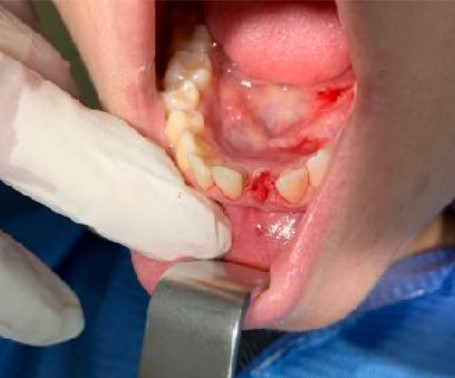

1 - UN CASO INCISIVO

Frattura di elemento incisivo inferiore 31 e riabilitazione implantare